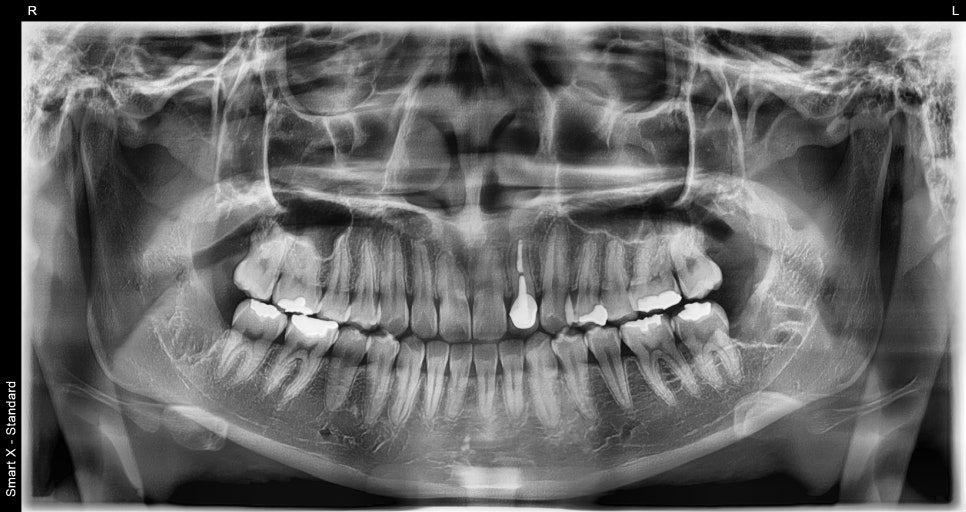

📸 X-ray after extraction

This is a panoramic X-ray taken after all four wisdom teeth were extracted at once. You can see that the extraction site has been neatly cleaned up.

Before surgery, the wisdom tooth was deeply impacted in the bone and very close to the nerve, so a careful surgical approach was necessary.

After surgery, it is recovering cleanly, and the procedure was completed without nerve damage. 😊